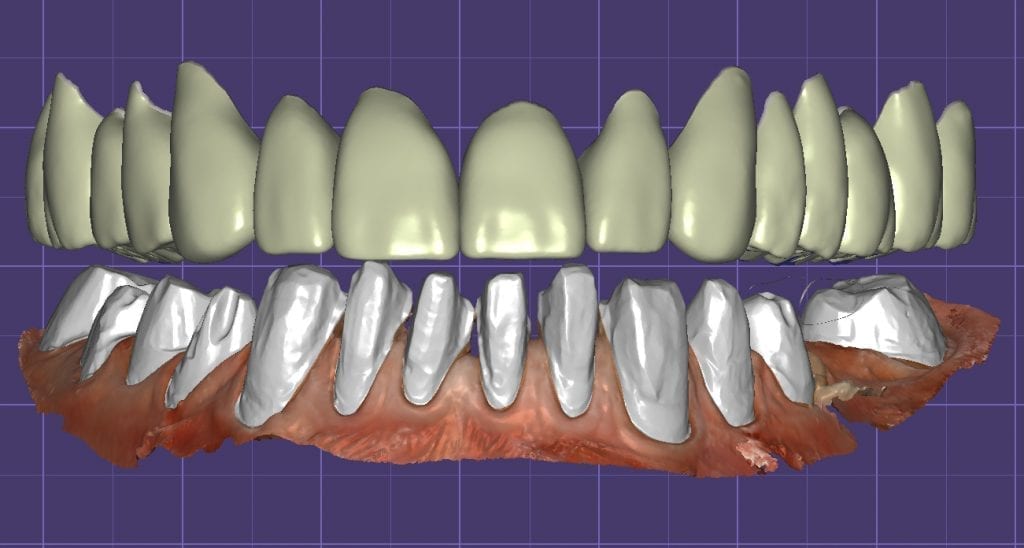

Over the course of a few appointments, the vertical dimension was reduced and the temporaries were adjusted to the patient’s desires. The new upper and lower arch were captured with the Medit i500 and the jaws were related to each other.

This was then imported into exocad where the prepped arches from a few weeks prior were force matched to the new bite

After the upper jaw was related to the temps, the same was done with the lower arch. Great care was taken to make sure the arches were properly related to each other throughout the process